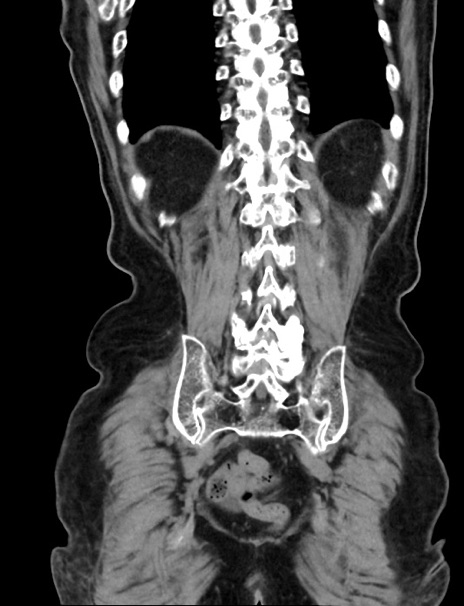

症例33(冠状断像)

【症例】70歳代 女性

【主訴】心窩部痛

【現病歴】延髄病変の精査・加療にて神経内科入院中。本日より心窩部痛あり。

【身体所見】右下腹部を中心に圧痛と反跳痛あり。

【データ】WBC 10900、CRP 0.02